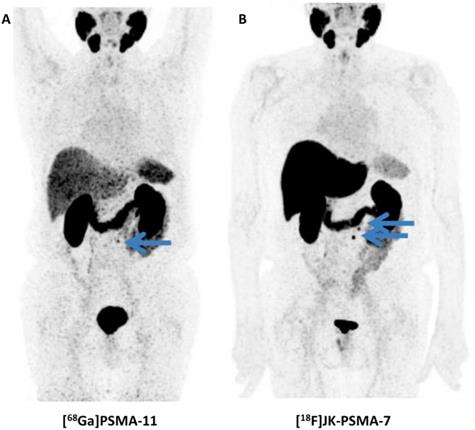

Figure 2

Head-to-head comparison of maximum intensity projections of [68Ga]PSMA-11 and [18F]DCFPyL in a patient with rising levels of prostate-specific membrane antigen. For [18F]DCFPyL, additional PSMA-positive supradiapragmatic lesions are noted. Modified from Dietlein et al. [18], © the authors (2015), published under the terms of the Creative Commons Attribution 4.0 International supradiaphragmatic (http://creativecommons.org/licenses/by/4.0/).

Not surprisingly, [18F]DCFPyL outperformed other molecular imaging agents (99mTc-methylene diphosphonate bone scan, Na18F PET/CT) for lesion detection in patients with PCa. In a 45-year old man with suspected oligometastatic PCa, 87 definitive sites of non-physiologic [18F]DCFPyL accumulation were detected, while planar bone scan detected only 12 supicious sites and Na18F PET/CT 39 lesions [50]. The same research group also reported on the superiority of [18F]DCFPyL compared to conventional imaging on a larger basis. In a secondary analysis of the first nine patients imaged with [18F]DCFPyL, 138 definitive sites of [18F]DCFPyL uptake were recorded, while only 1 was classified as equivocal. This was in contradistinction to CT-and-bone-scan based disease patterns (30 definitive, 15 equivocal). Taking into account intra-patient clustering effects, lesions which have been rated as negative/equivocal on conventional imaging would be positive on [18F]DCFPyL in the vast majority of the cases (0.72, based on a generalized estimating equation regression analysis) [5]. In addition, [18F]DCFPyL has also been tested in a head-to-head comparison with its 68Ga-labeled counterpart, namely [68Ga]PSMA-11. In 14 patients with biochemically recurrent disease, the 18F-labeled radiotracer identified more sites of disease in three patients and those findings were also further corroborated semiquantitatively (higher maximum SUV (SUVmax) and tumor-to background ratios). The results of this study suggest [18F]DCFPyL is an attractive alternative to 68Ga-labeled compounds (Figure 2) [18].